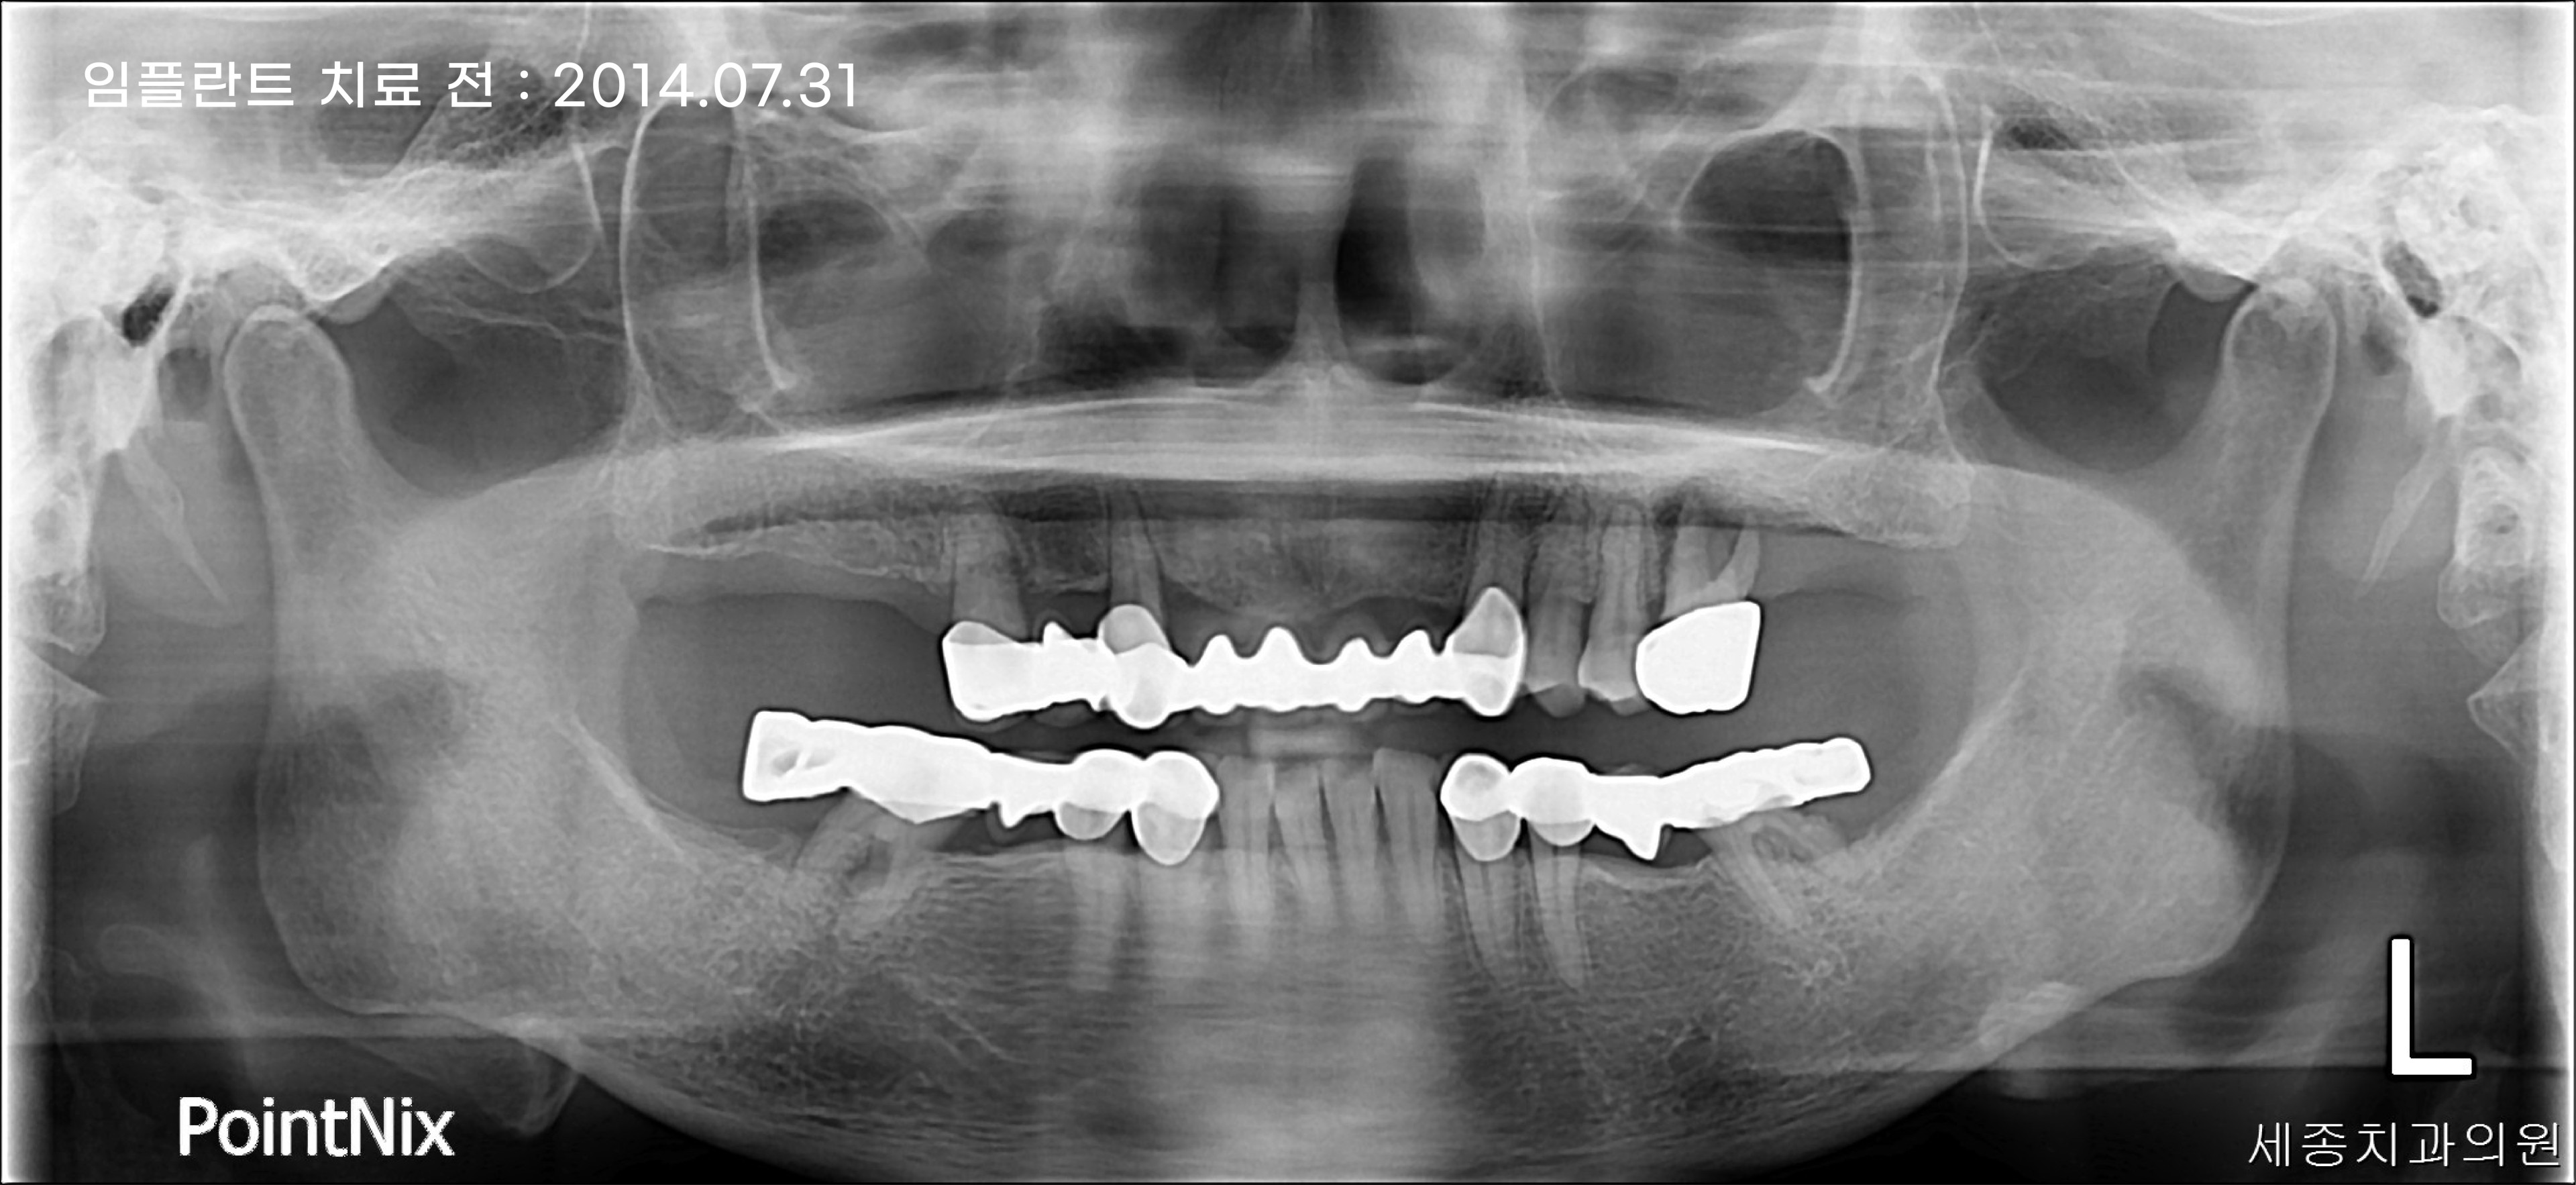

치아 브릿지 대신, 임플란트로 상실 치아 회복

부산임플란트 세종치과 10주년 기념으로 2014년에 내원하신 환자분의 케이스를

통해 브릿지와 임플란트의 장단점을 알아보는 시간을 가져보도록 하겠습니다.

환자분의 경우 첫 내원을 했을 때 치아를 상실한 부위를 치아 브릿지로 치료를 하신 상태였는데요.

위의 파노라마 사진에서 볼 수 있듯이, 하악 기준 상실한 치아의 개수는 6개이지만 임플란트는 4개만 식립하여

1. 시술 비용 감소 2. 통증 감소 3. 회복 기간 감소 등의 장점을 얻을 수 있습니다.